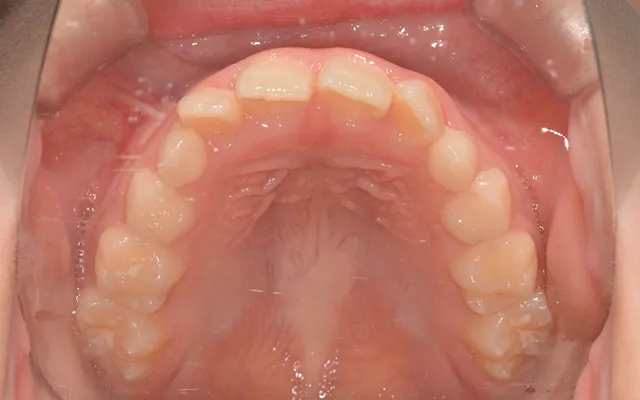

- BEFORE

-